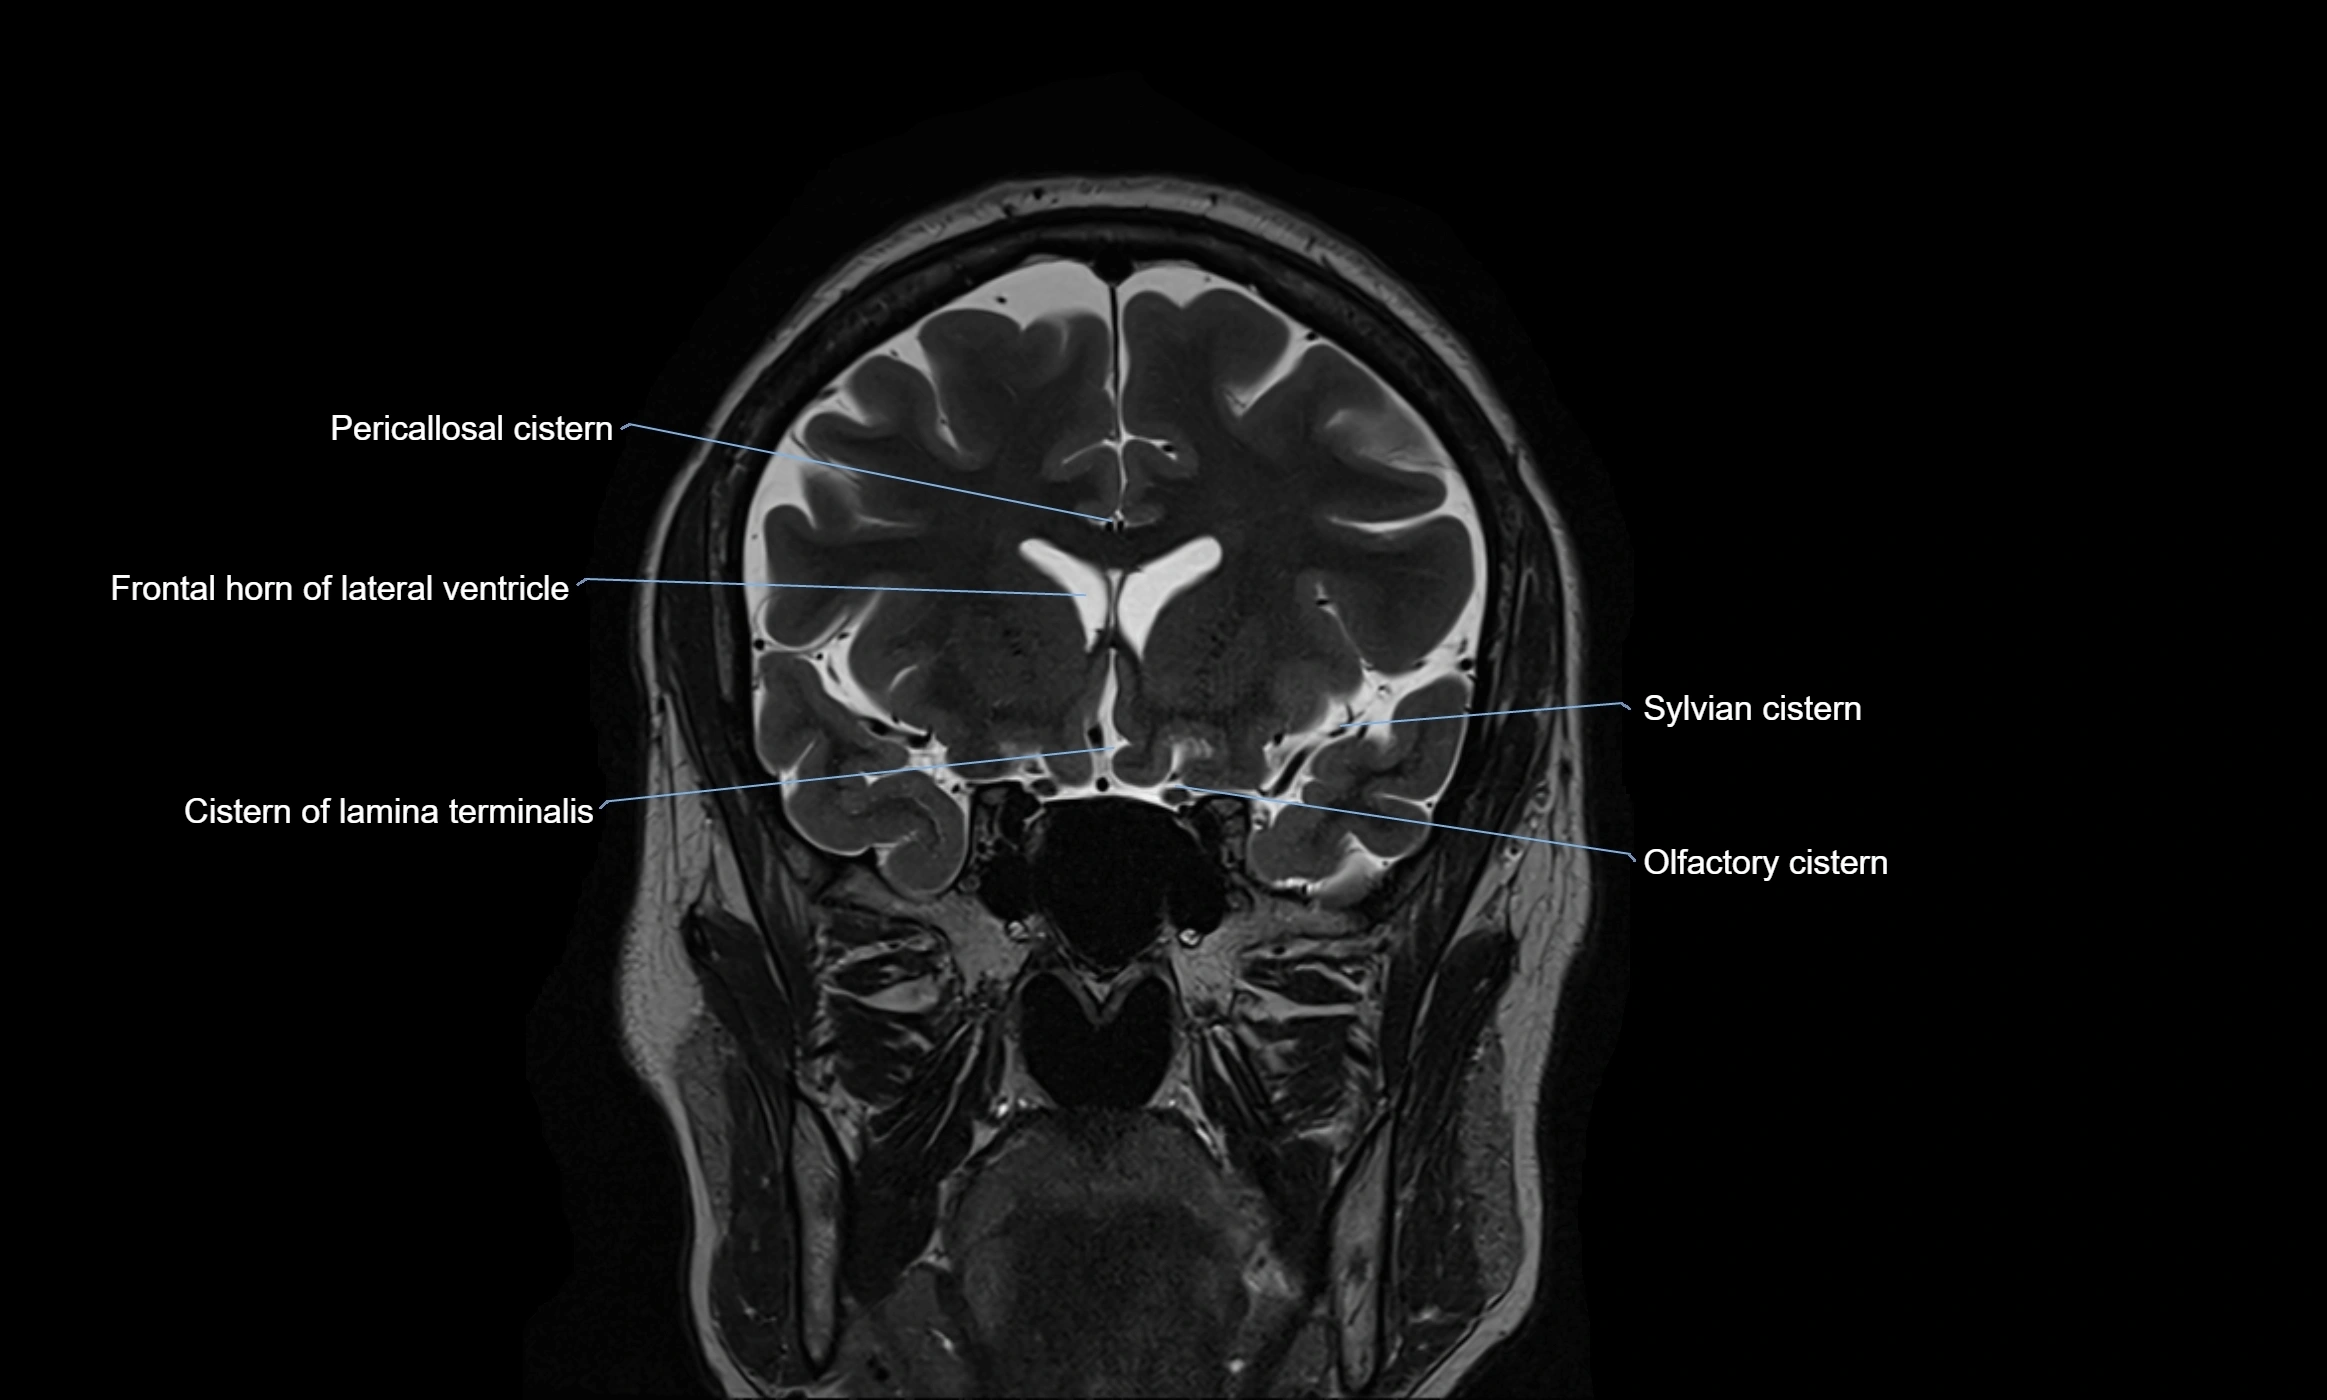

MRI images

image